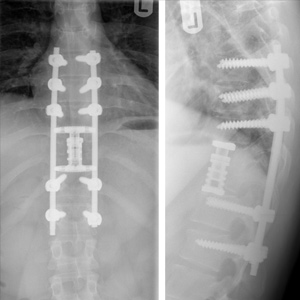

Spinal stenosis (Lumbar) Spinal stenosis (Cervical) Spinal stenosis (Thoracic) Lumbar Disc Herniation Spondylolisthesis Cervical Foraminal Stenosis Vertebroplasty Lumbar Fusion Anterior Cervical Fusion (ACDF) Posterior Cervical Fusion Thoracic Fusion Revision Lumbar Fusion Surgery Facet Joint Cyst Spinal Tumour Minimally Invasive Lumbar Fusion (XLIF) Minimally Invasive Lumbar Fusion (ALIF) Lumbar Fusion (TLIF) Thoraco-lumbar Fusion Lumbar Corpectomy Complex Lumbar Spine Surgery (Spino-pelvic fixation) Complex Cervical Spine Surgery Complex Thoracic Spine Surgery Occipito-cervical Fusion Minimally invasive surgery for thoracic disc herniation Other Related Topics